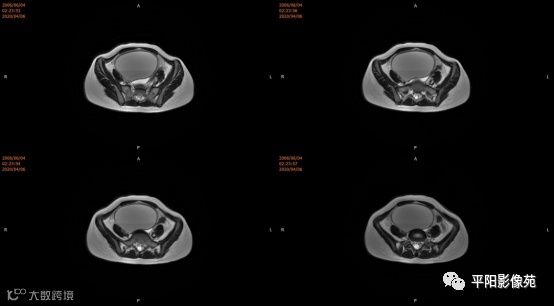

患者,女,13岁

主诉: 下腹部胀痛2+月,加重1天

现病史: 患者月经未来潮,2+月前无明显诱因感下腹部憋胀,间断胀痛,可忍耐,伴排便困难,自认为便秘引起腹胀,未在意。近1+月腹胀、胀痛次数增加,觉下腹部逐渐增大,小便正常。

您的诊断?

3.CT检查 对子宫、阴道的界限区分有一定限制,对子宫内膜、肌层难以分辨,故CT对子宫先天性异常的研究较少。阴道闭锁时,若宫腔内经血潴留,可见液性低密度聚集,子宫肌层密度均匀。

4.MRI检查 对软组织分辨率好,能够清晰区分子宫及阴道,对子宫内膜、结合带、肌层可清晰分辨;能明确子宫、宫颈、阴道结构异常的部位、范围、性质等。宫腔内经血潴留时,宫腔内见短T1长T2信号。